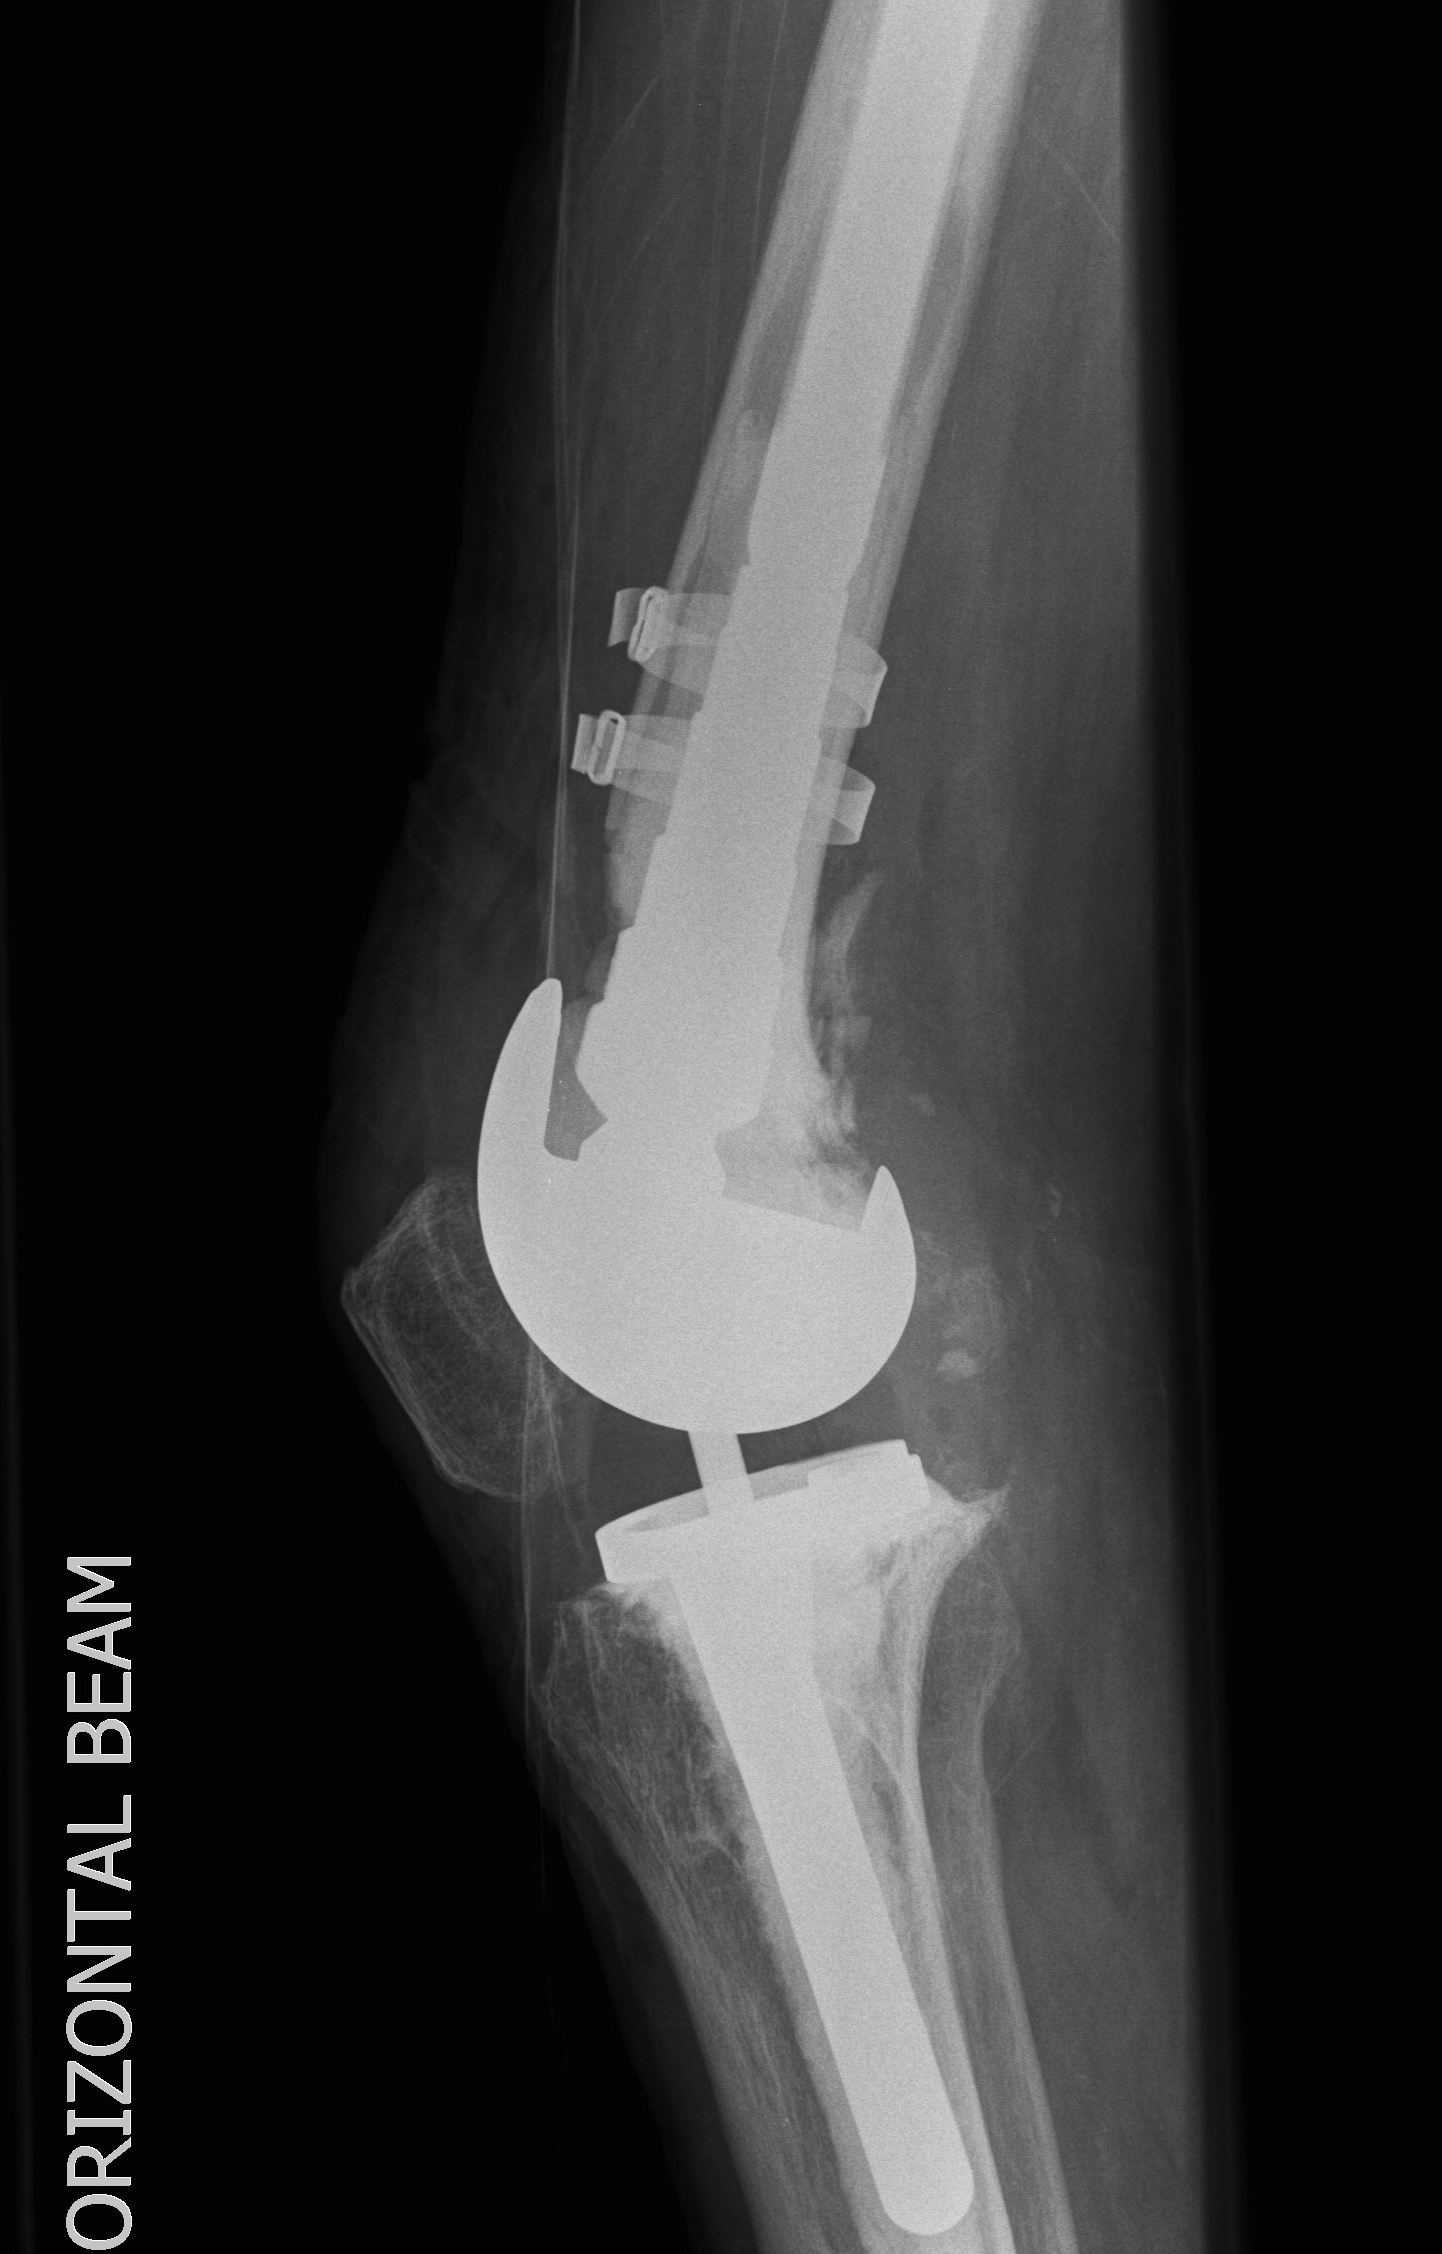

Howard et al JBJS Am 2011

- femoral tantalum components in 24 knees followed for averag 3 years

- knee society score average 81

- all well fixed with no complications